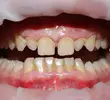

Dental Caries

Dental Crowding

Developmental Deficiencies of the Tooth, Jaw, and Facial Region